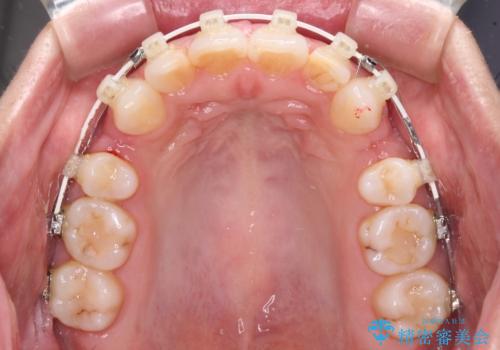

- 矯正装置

- 審美装置

- くちばしのような前歯の突出感を気にして来院された患者様です。

上下左右第一小臼歯4本を抜歯して、積極的に口元を引っ込めるよう、ワイヤー装置にて矯正治療を行うこととしました。